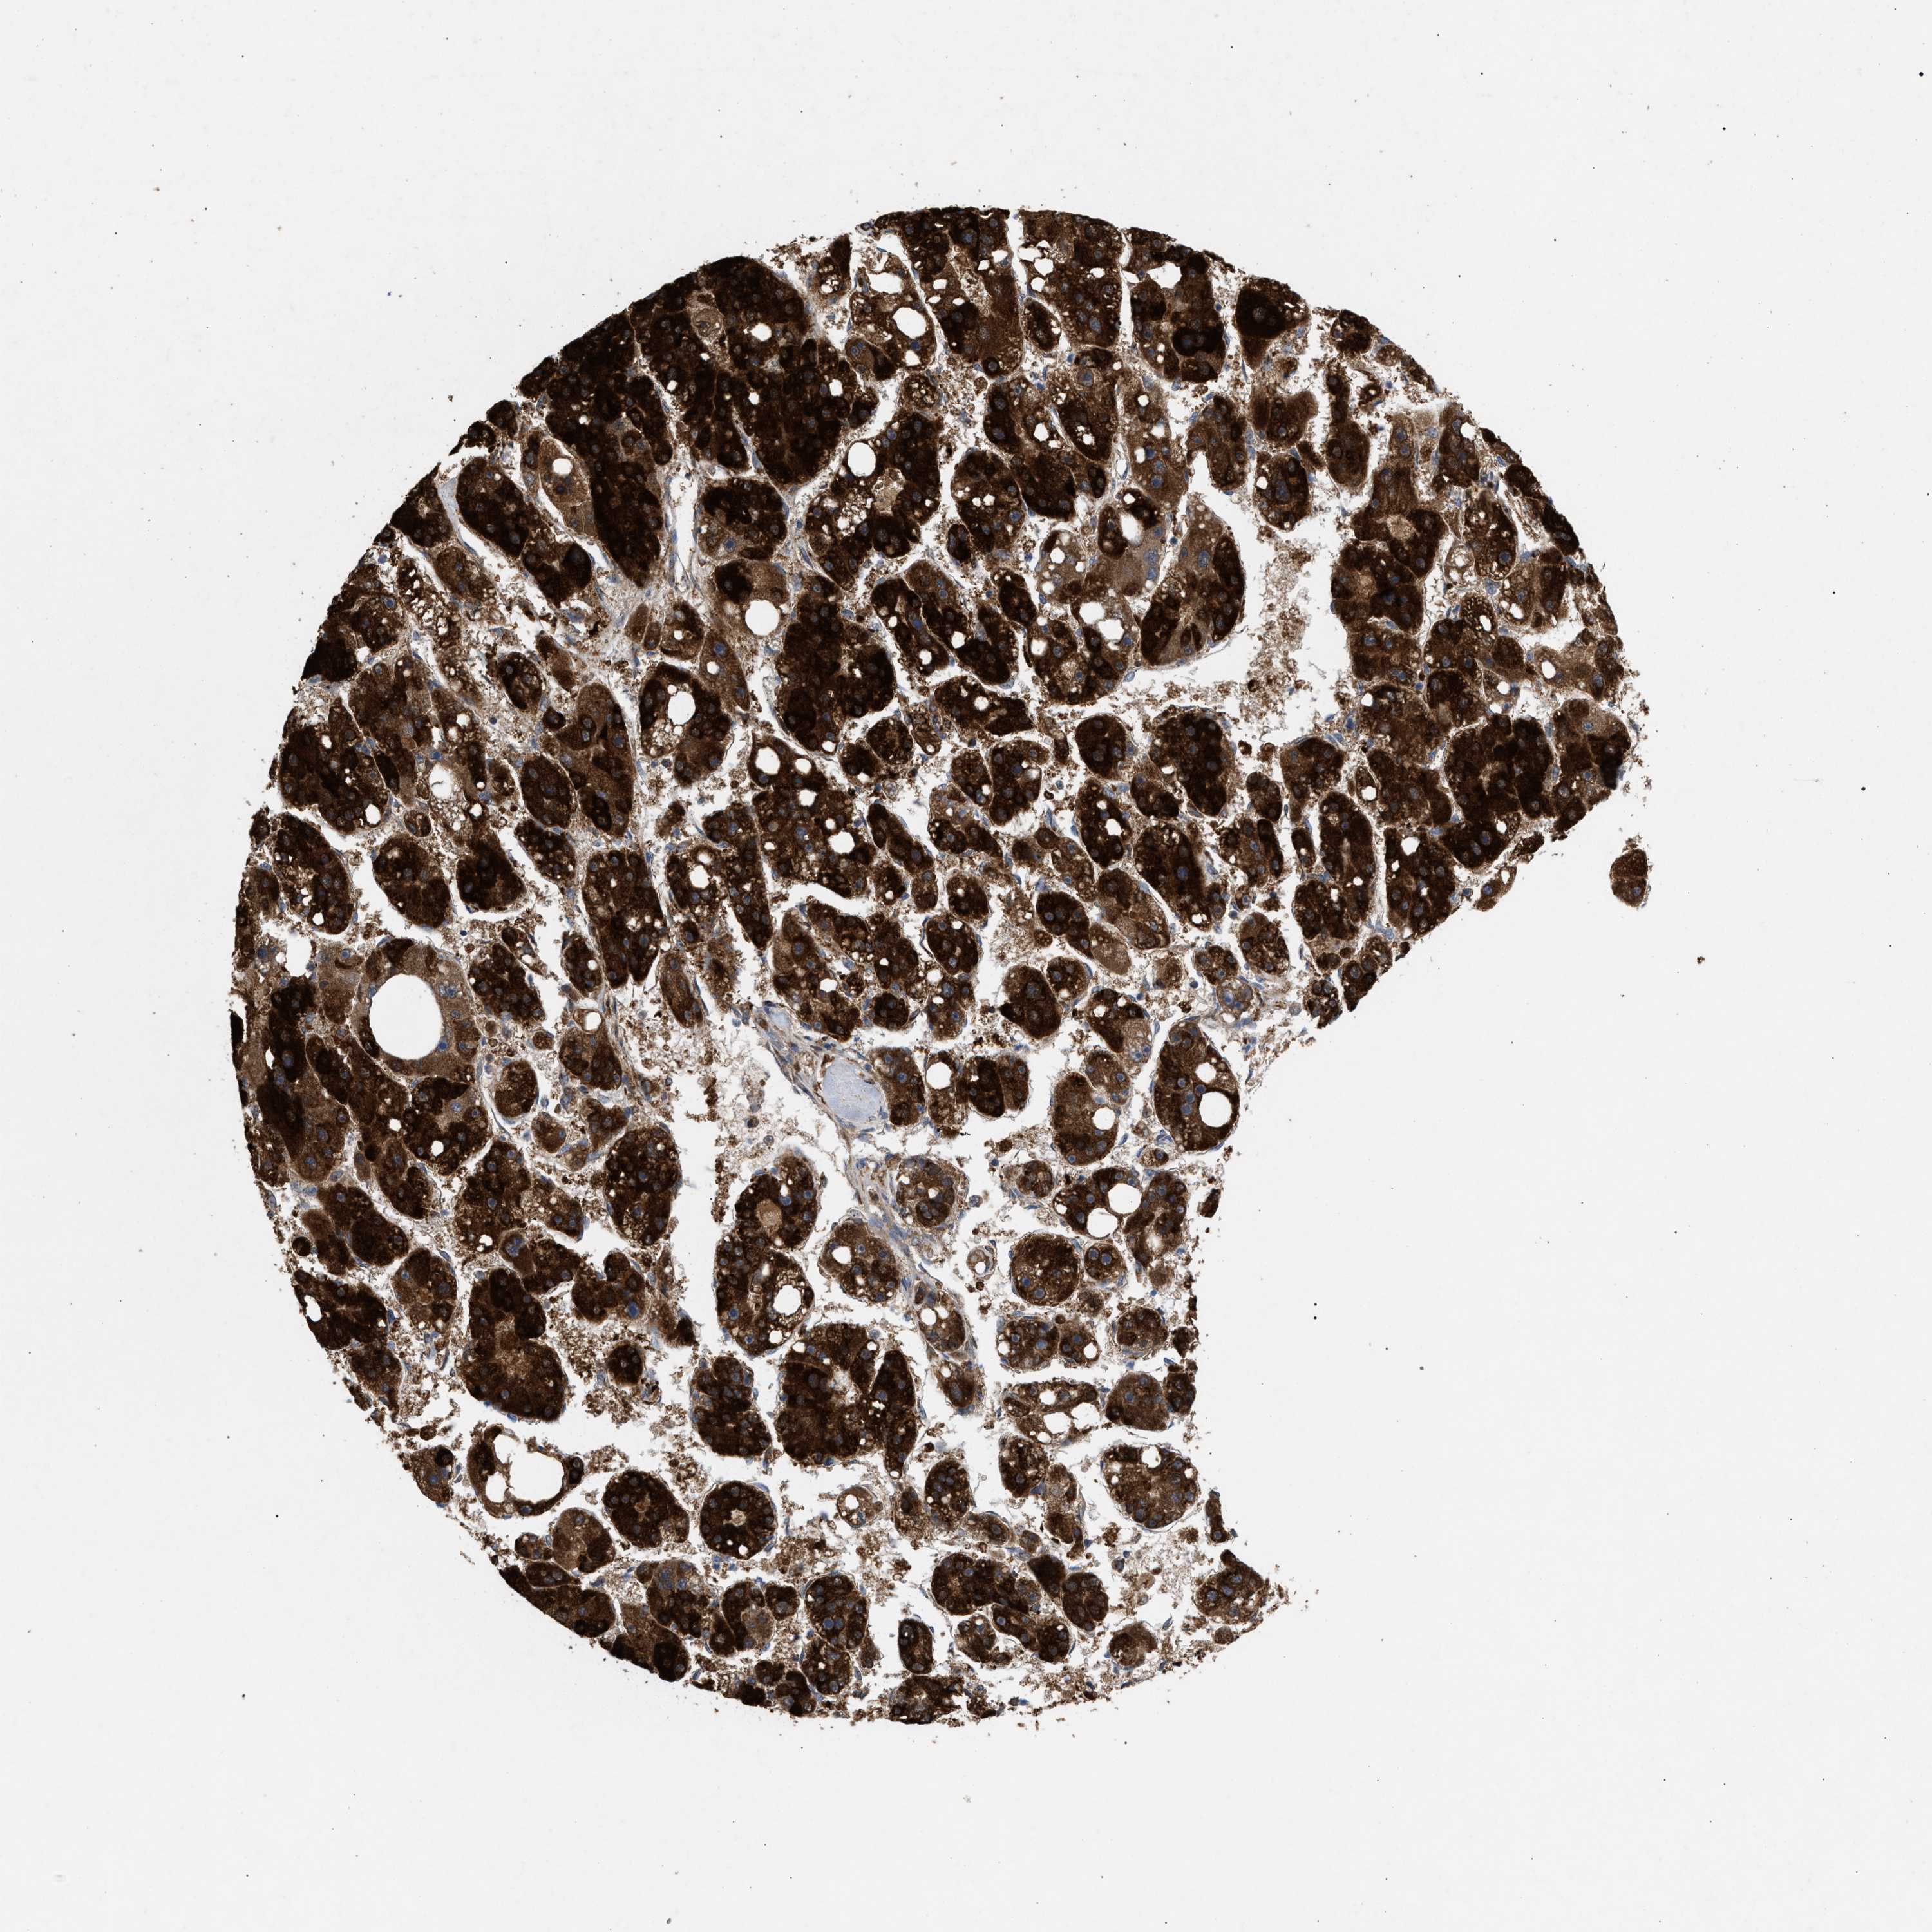

LIVER CANCER - Protein expressioni

A mouse-over function shows sample information and annotation data. Click on an image to view it in a full screen mode. Samples can be filtered based on level of antibody staining by selecting one or several of the following categories: high, medium, low and not detected. The assay and annotation is described here.

Note that samples used for immunohistochemistry by the Human Protein Atlas do not correspond to samples in the TCGA dataset.

Antibody stainingi

Antibody staining in the annotated cell types in the current human tissue is reported as not detected, low, medium, or high, based on conventional immunohistochemistry profiling in selected tissues. This score is based on the combination of the staining intensity and fraction of stained cells.

Each image is clickable and will lead to virtual microscopy that enables deeper exploration of all samples and also displays staining intensity scores, fraction scores and subcellular localization as well as patient and tissue information for each sample.

Antibody HPA019369

Antibody HPA021323

Staining

High

Medium

Low

Not detected

Intensity

Strong

Moderate

Weak

Negative

Quantity

>75%

75%-25%

<25%

None

Location

Nuclear

Cytoplasmic/membranous

Cytoplasmic/membranous,nuclear

Cholangiocarcinoma

Carcinoma, Hepatocellular, NOS